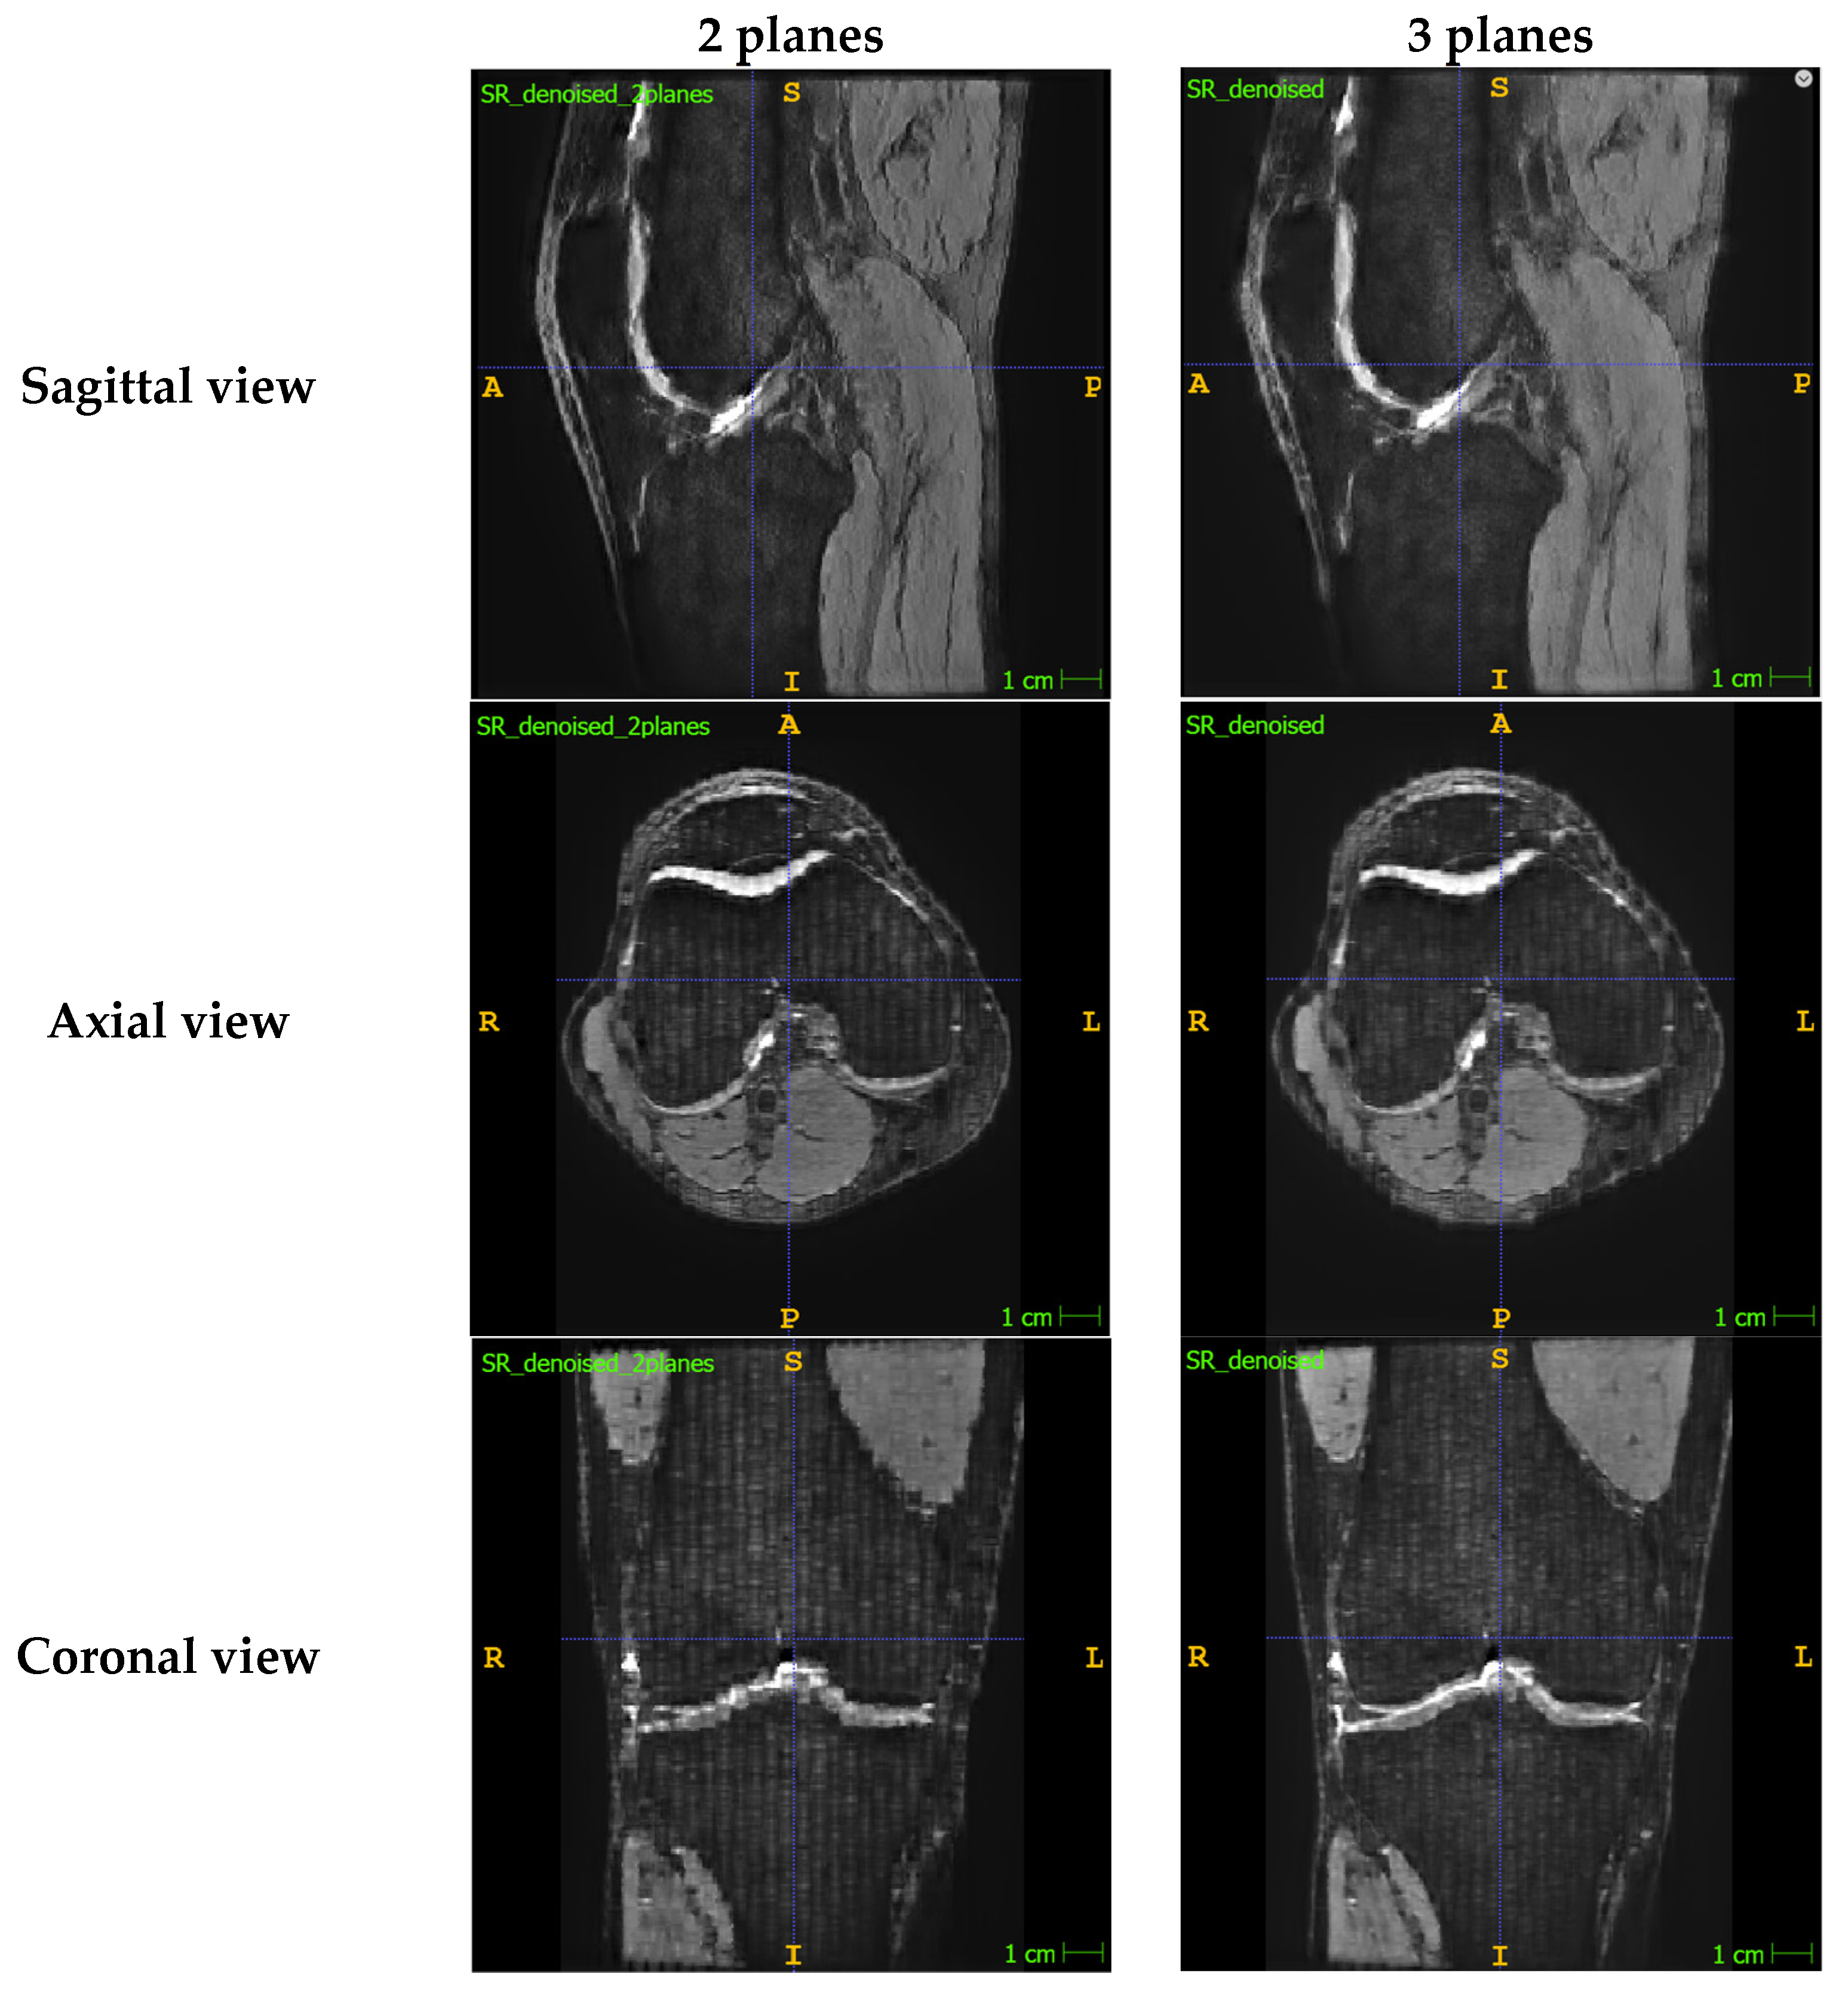

Appendix A.1. Presenting the Comparison between SR Images Reconstructed with Two Planes vs. Three Planes